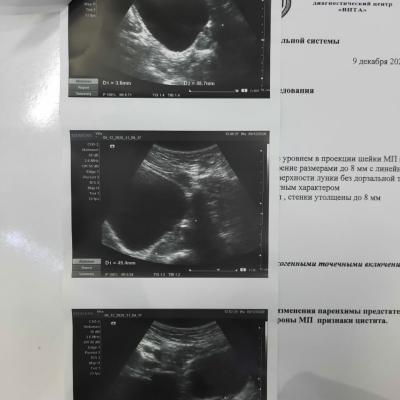

Застудил ноги, начал бегать в туалет, пошел в больницу, поставили диагноз хрон простатит и начали лечить, , лечили толку нет и после этого началась струя в разные стороны, сменил врача — то же самое, лечили простату. Мочевой не смотрели. Думали стриктура — сделали уретроцистоскопию, ее нет. Была чуть воспалена шейка. Сейчас обнаружили зппп, вылечили. Их нет. Симптомы остались, воспаления сняли. В узи выявили какую-то лунообразную впадину. Посмотрите пожалуйста, назначили лидазу/дистрептазу и амикацин. Анализы все чистые, флоры нигде нет.